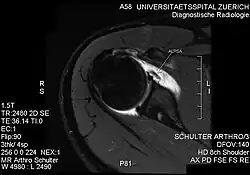

| PD-weighted MRI with fat saturation of the shoulder showing an ALPSA lesion |

An ALPSA (anterior labral periosteal sleeve avulsion) lesion is an injury at the front of the shoulder associated with shoulder dislocation.[1]